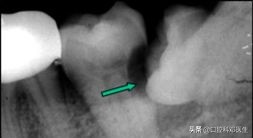

经过医生的检查发现,原来这几个病人都是因为长智齿后反复发炎,炎症通过间隙扩散至面部皮下,致脸上长出了很大的脓包,而且一直不消,不得不戴上口罩才敢出门!

智齿行凶过程图

接下来医生要做的事,就是在脸上切开,把脓液给放出来,然后等炎症缓解后把凶手“智齿”给绳之以法!